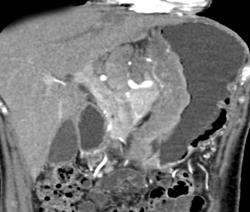

Gastric Lymphoma